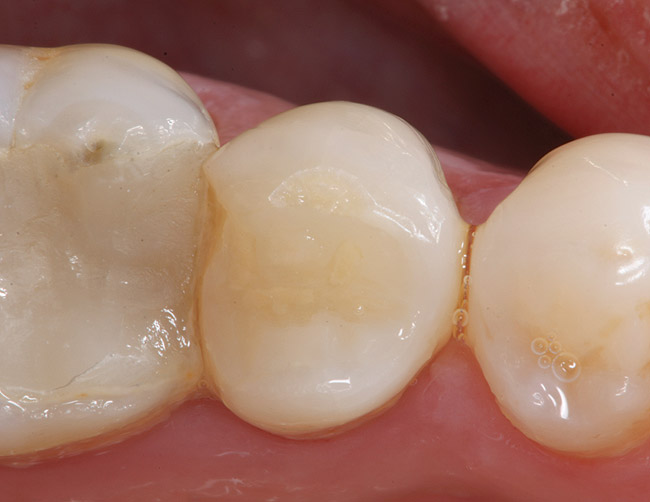

Fig. 5 Defective margins. Mandibular second molar with a Class II composite resin with a defective facial–gingival margin.

Figure 5  Defective margins. Mandibular second molar with a Class II composite resin with a defective facial–gingival margin.